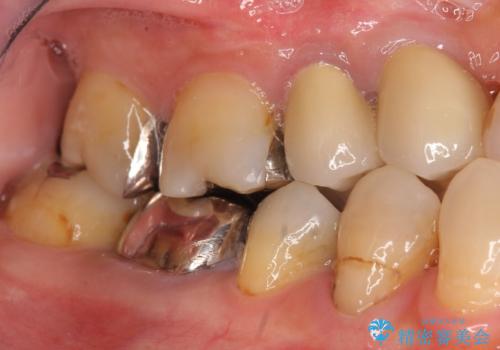

- 奥歯の違和感を主訴に来院された患者様です。

右下の銀歯(右下6)を除去したところ、虫歯が深く保存不可能な状態でした。

ブリッジ、インプラント、入れ歯の3つの選択肢を提案したところ、ブリッジをご希望されました。